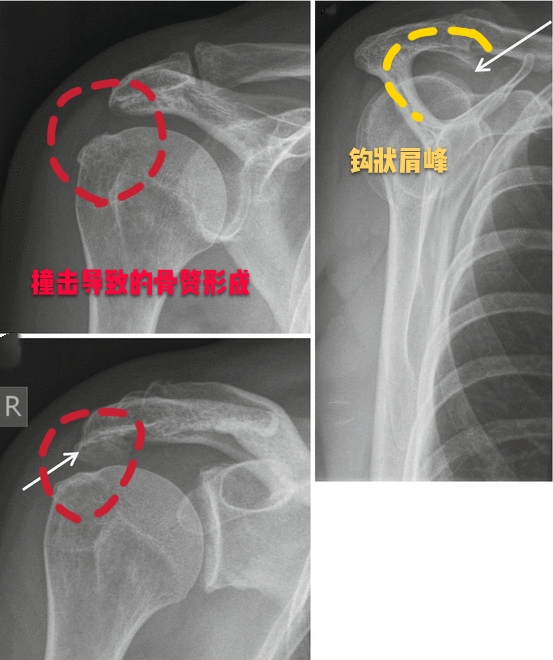

这个房檐形态不是特别的一样,每一个人都有各自的肩峰形态,一般情况下我们的肩峰形态有三种,1种是平的,第2种是略弯曲的,第3种就是钩状的,现在也有人发现有一些人的肩峰是向上翘的,但是这种肩峰不会诱发特殊的症状。主要会导致我们出现肩痛的问题,是三型肩峰,也就是钩状的肩峰,因为向下呈钩状的肩峰,在我们的肩关节活动过程当中,导致肩关节间隙的狭小,会在肩关节活动的过程当中导致撞击!尤其是肩关节做一些前屈、外展、上举的动作时,比如抬起胳膊够比较高的东西,比如羽毛球的挥拍动作。

●肩关节撞击综合征导致的肩痛:肩关节撞击综合症导致的疼痛,往往由固定的动作诱发,疼痛不是特别的明显时,往往不是特别受到重视,有些患者在做特殊动作,比如挥拍动作的时候,会感觉肩关节内有的响声,症状比较明显的时候,会伴有疼痛。

通常情况下进行肩关节的x线检查或者是核磁检查,可以帮助我们明确肩关节是否存在着肩峰形态的异常以及撞击。

但如果患者经过了保守治疗以后症状仍然特别严重,有可能要进行肩关节镜手术治疗,将钩状的肩峰削平,去除撞击的因素,患者的症状也就会消失了。